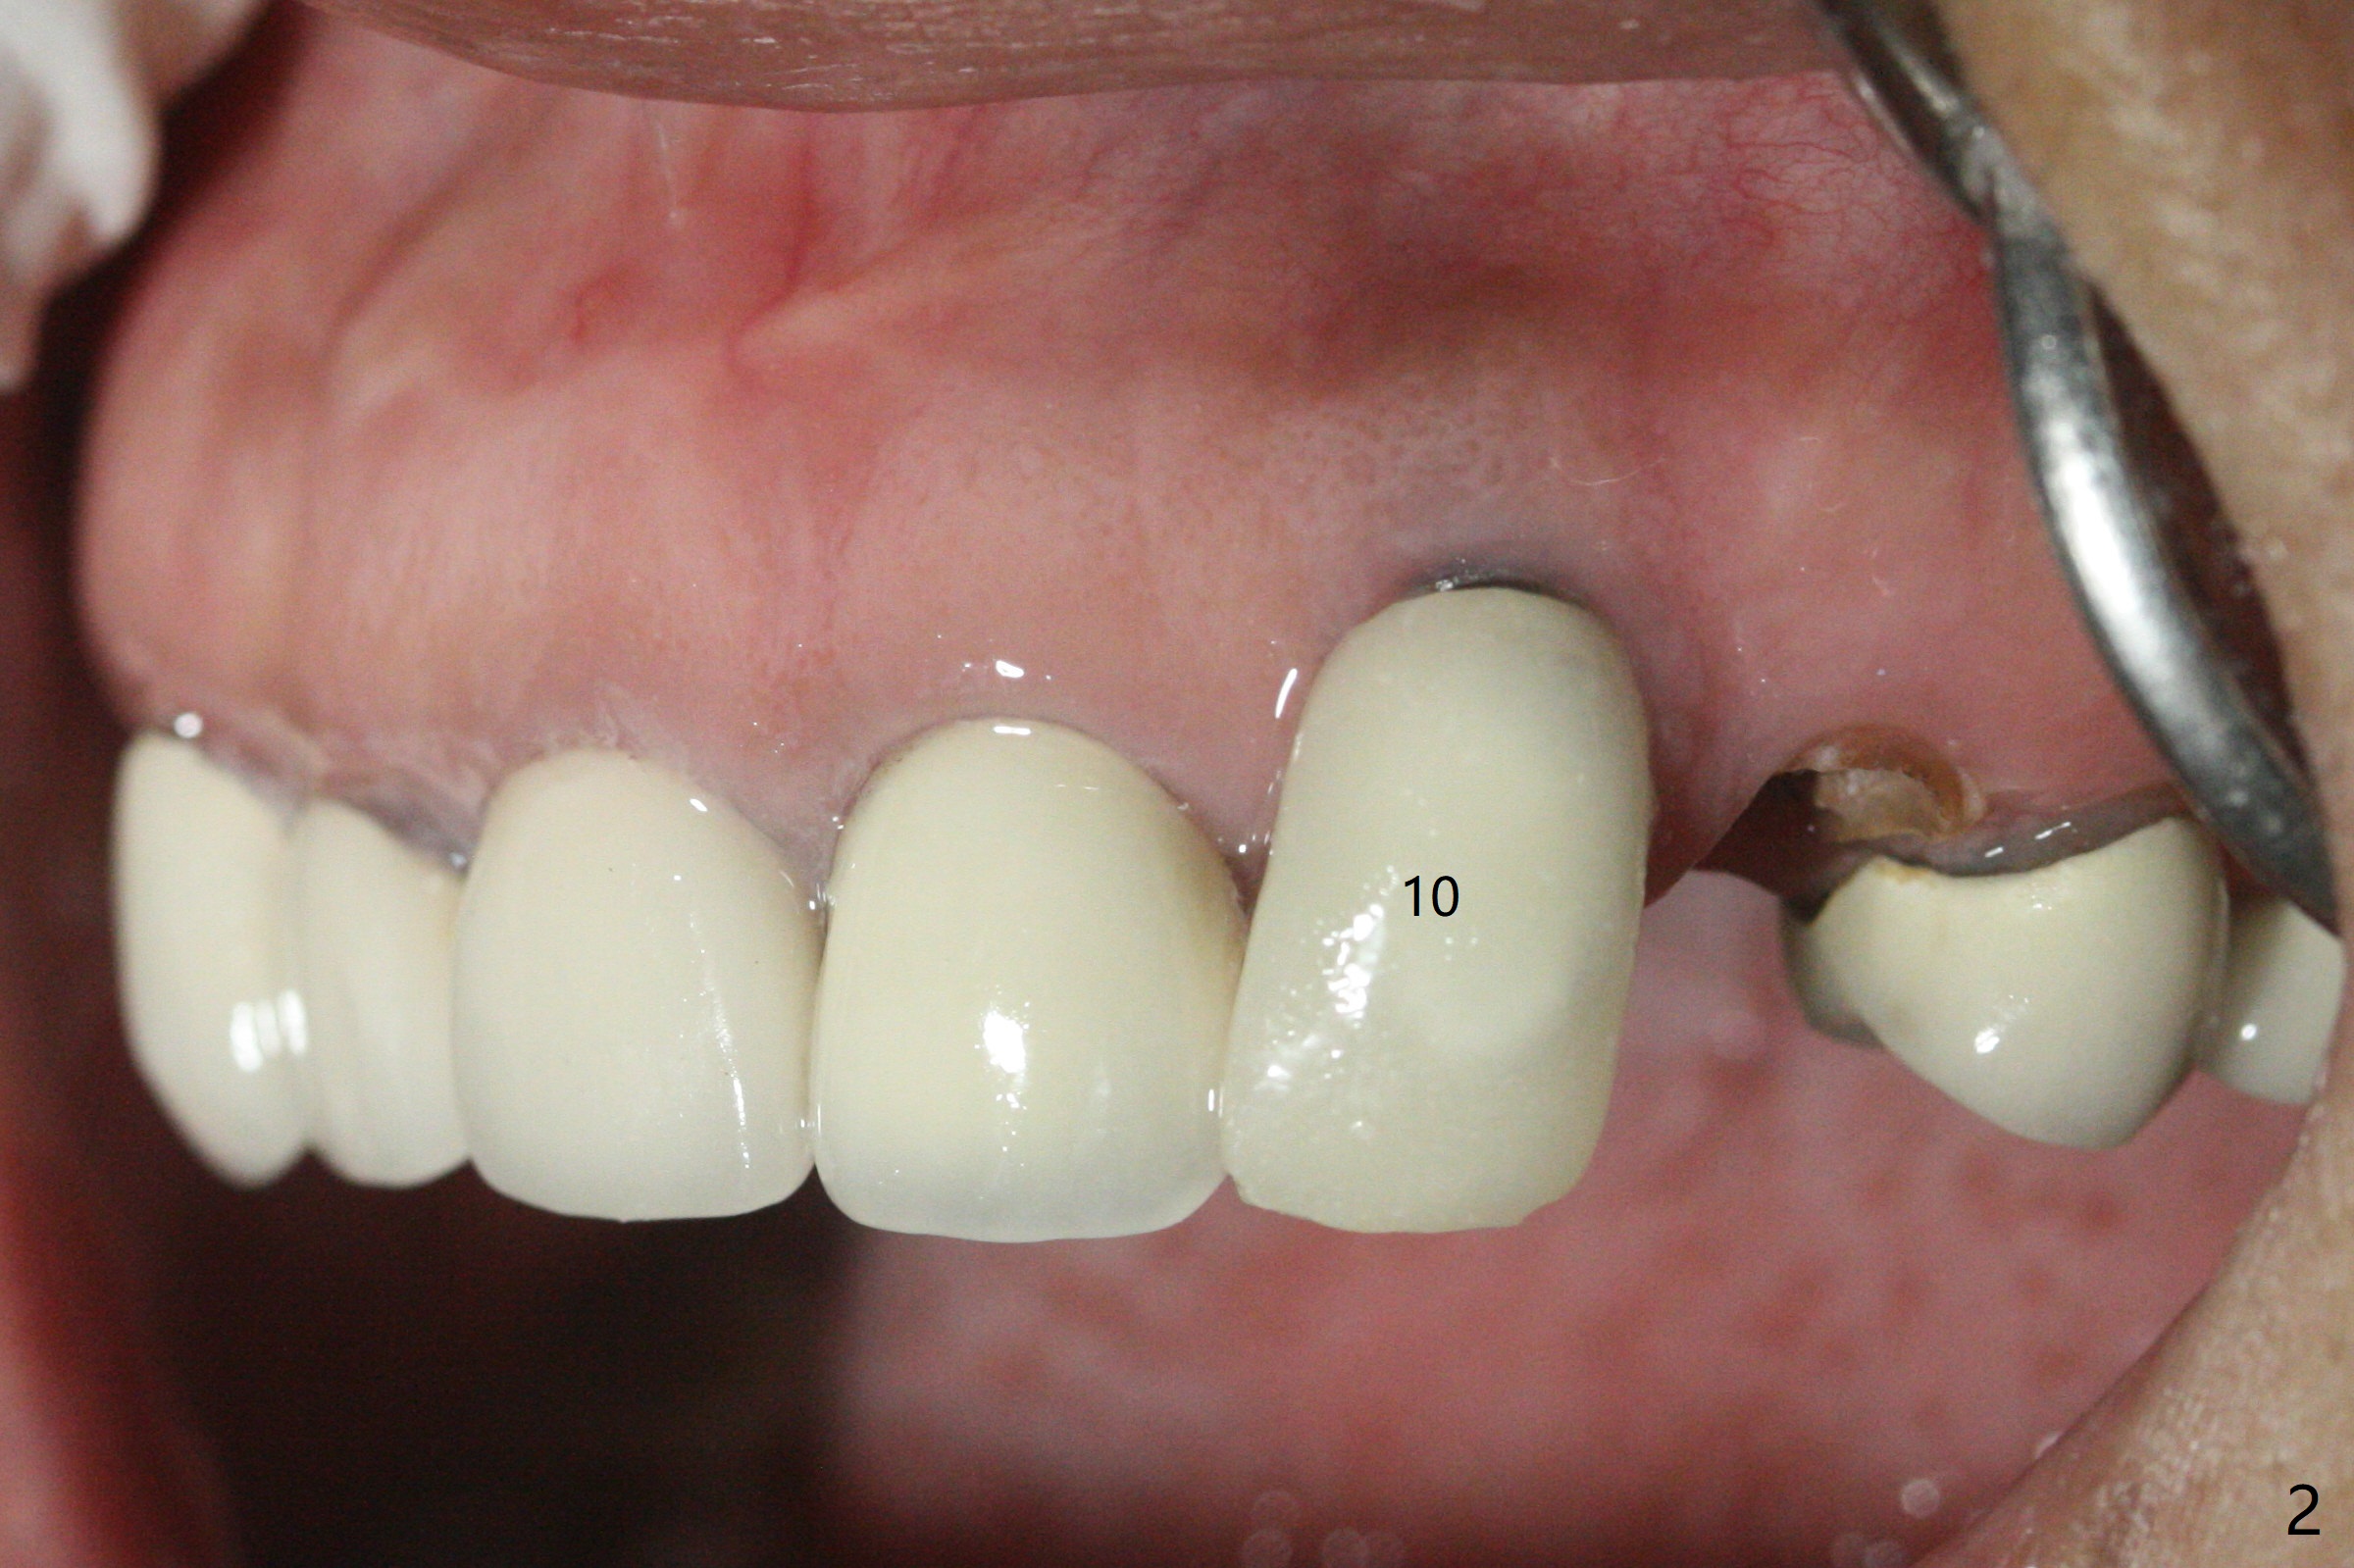

A 57-year-old woman presented to office with dislodged canine crown 10 months earlier (Fig.1). It was cemented. It dislodged again lately. She decides to have an implant and mentions looseness of the implant crown of the lateral incisor. Gingival recession is severe at #10 (Fig.2), while #11 has subgingival fracture (Fig.3). The recession is related to suboptimal angulation and buccal placement of the fixture (Fig.4), while the implant at #11 will be narrow and be placed with sufficient remaining buccal and palatal bone (Fig.5). Socket shield may be done. Prepare gingival retractors. In fact socket shield is not done because of caries in the root stump.